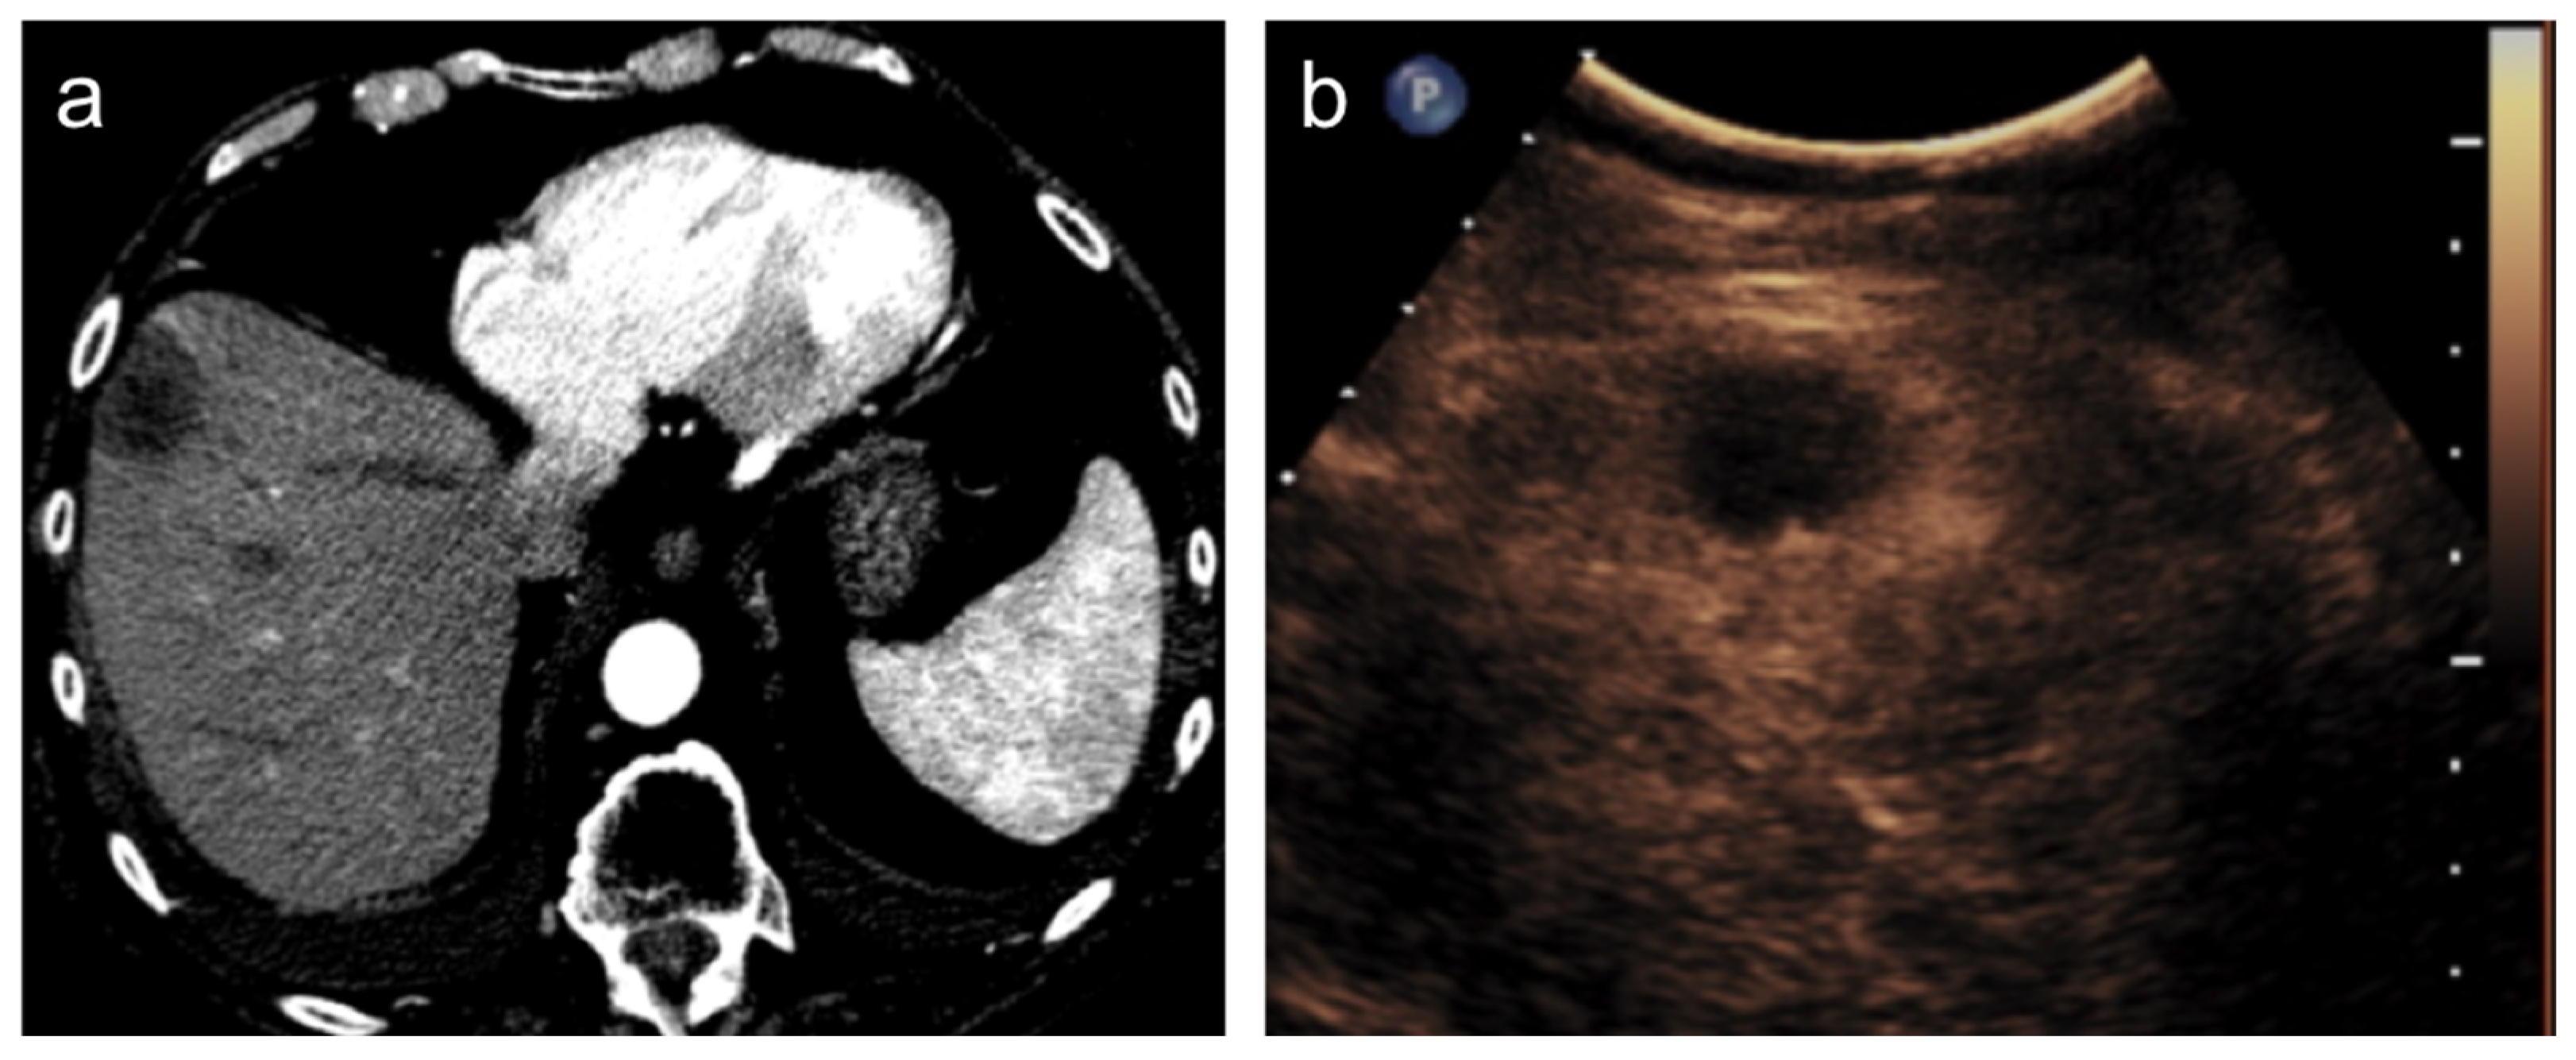

- Eisenbrey, J.R.; Gabriel, H.; Savsani, E.; Lyshchik, A. Contrast-enhanced ultrasound (CEUS) in HCC diagnosis and assessment of tumor response to locoregional therapies. Abdom. Radiol. 2021, 46, 3579–3595. [Google Scholar] [CrossRef] [PubMed]